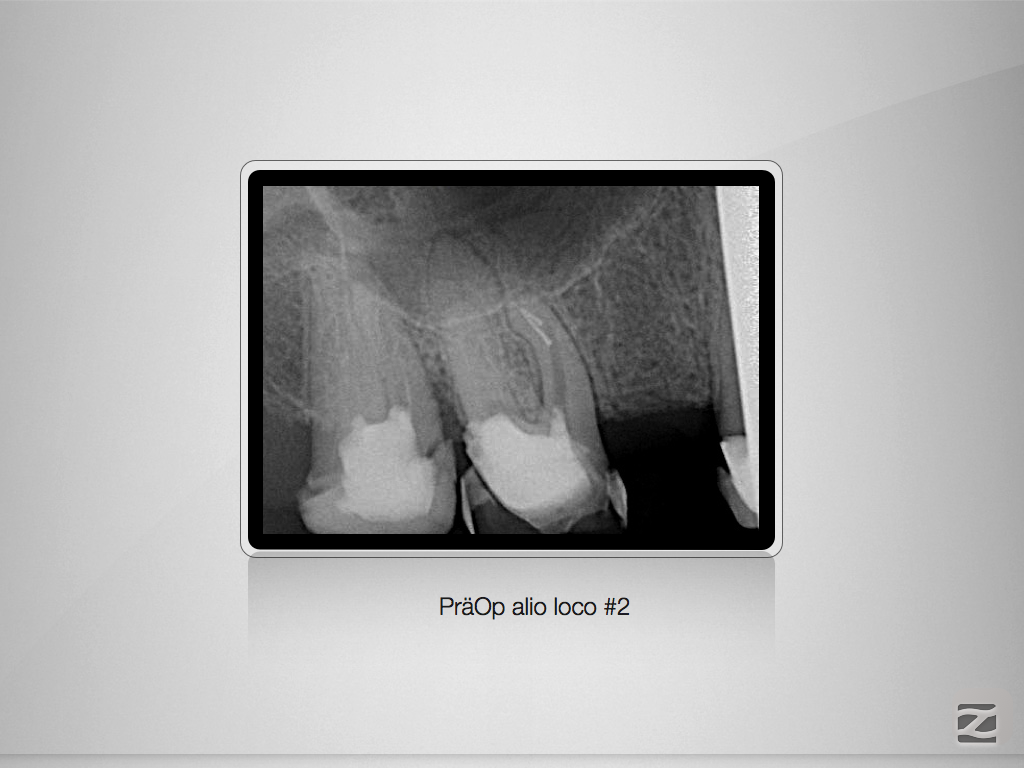

16d-002

1024 × 768

Standards